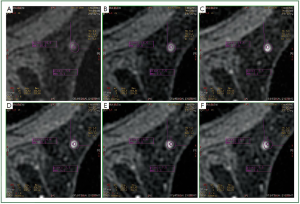

That observation motivated us to conduct a retrospective study of 115 MRMs in order to find the reason for this artifact and to find out ways of avoiding it. For each lesion, the ROI was placed manually in the six images, which correspond to the six phases of the dynamic acquisition, and the signal intensity was measured. Moreover, it was ensured that the ROI was positioned in the same area of the lesion by measuring the distances from the periphery of the ROI to stable points on skin, muscle, ribs and sternum that appear at the image (Figure 2) due to the fact that these points do not significantly change during enhancement in dymanic sequences. It must be stated that these stable points had a specific characteristic, which could be easily identified in all the phases. Furthermore, at least two such stable points were used in positioning the ROI in each phase based on both the distance and angle between the periphery of the ROI and each stable point. In homogeneous lesions, the ROI was positioned in the center of the lesion and subsequently the measurements from the stable points were used to verify the correct of position of the ROI. Skin and muscle have a homogeneous enhancement, whereas the periphery of sternum and ribs have no enhancement whatsoever since they are composed of ossified tissue. Finally, the kinetic curves were manually derived based on the signal intensity-to-time. The manually derived curves were compared to the derived curves by the software of the system regarding their type (Figure 3). The whole procedure was performed by the same radiologist with experience in breast MRI.

Figure 2. Six images (A-F) representing the different phases of the dynamic image acquisition at the same position. In the third phase of the dynamic sequence (C), two ROIs (a large peripheral and a small central) were delineated. The two ROIs were placed in the rest five phases using the manual procedure based on the distances from stable reference points (muscle and skin) that were measure in phase C. Note that there is no shift of the ROI in the different phases of the dynamic study.